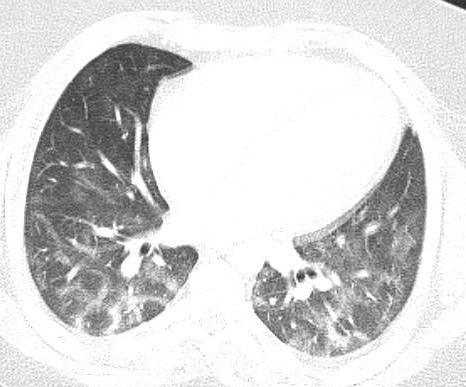

Acute Pediatric COVID-19: CT

21 Imaging of Covid 19 infection in children

3 Phases

Early: "Halo" sign

Local infection

Progressive: Diffuse GGO

Developed: Consolidation

Surr vasc congestion

Inflammation - adj alveoli

Alveoli fill with fluid/cells

Imaging of Covid 19 infection in children

Local infection Surr vasc congestion